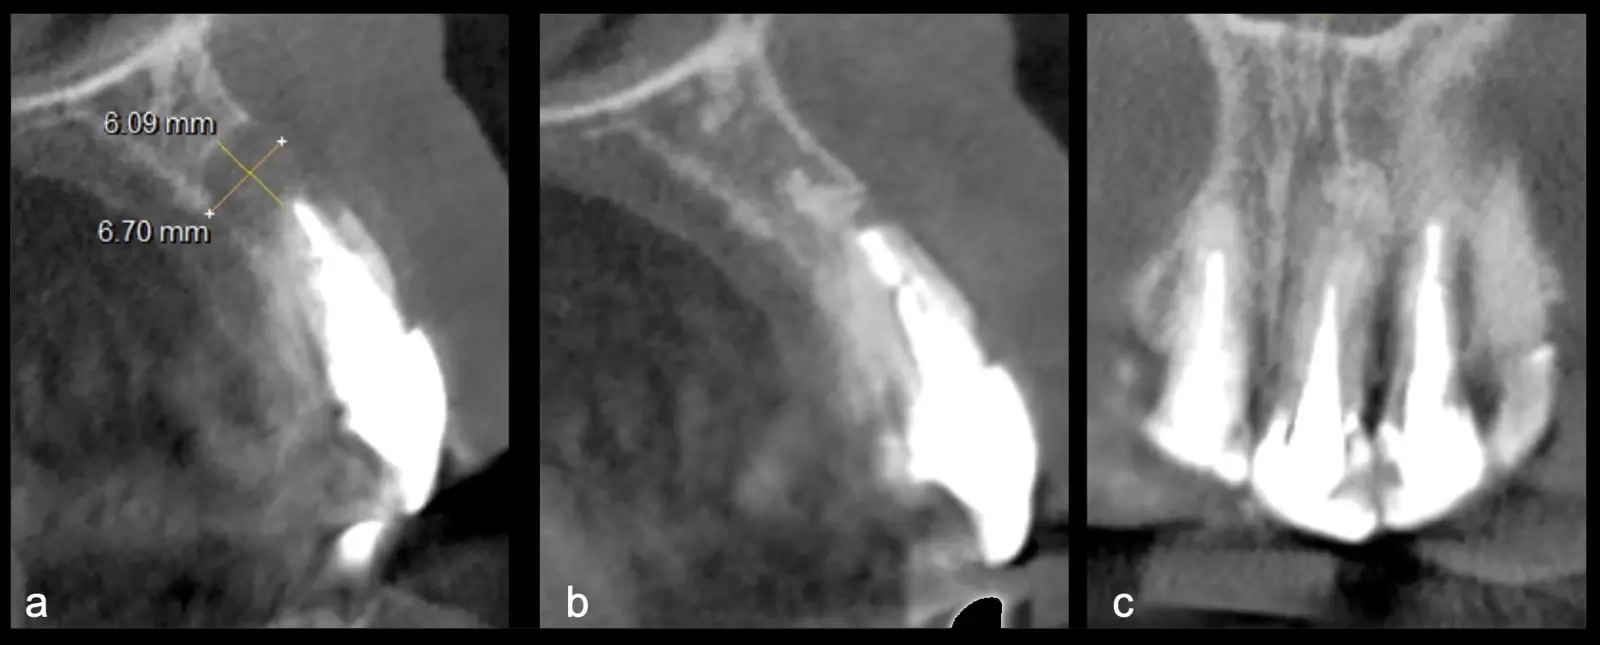

La microcirugía endodóntica apical busca conservar la mayor cantidad de longitud de raíz y de hueso circundante sano para no afectar la estabilidad de la pieza.11 Por ello, es ideal el uso de microscopios, elementos de magnificación, instrumental específico (insertos de ultrasonido endodónticos) y materiales de sellado eficientes para el tratamiento retrogrado. Su éxito es alto y evidencia una cicatrización ósea completa en el 74% de los casos al año de tratamiento.12 Cabe destacar que este logro está asociado también, a predictores propios de cada paciente, como la edad, tipo de pieza, profundidad de sondaje y extensión de la lesión.1 El uso complementario de la tomografía computarizada es resaltante como el instrumento imagenológico de elección para la etapa de planificación microquirúrgica,13 ya sea para una ejecución a mano alzada o con guías prefabricadas.14,15

Una vez limpia la zona apical, se corrobora la integridad de la raíz y se evalúa el grado de extensión de la lesión. Si el defecto óseo es pequeño, se procede a realizar la preparación del conducto y obturación retrógrada de ser el caso. Si el defecto óseo es de gran tamaño e inaccesible a los insertos, se procede a realizar un corte de por lo menos 3 mm de ápice radicular conteniendo los posibles conductos aún infectados11 empleando habitualmente insertos de borde aserrado con/sin marcas de medición para un trabajo seguro7 (Figura 7).